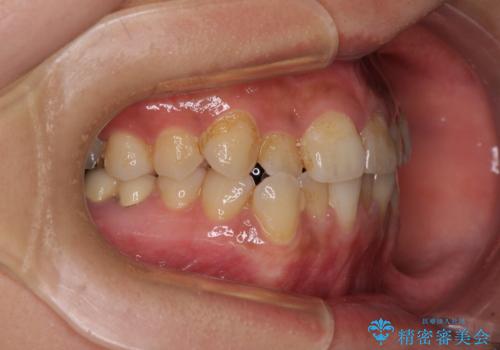

前歯のデコボコとクロスバイト インビザラインによる矯正治療

- 上下のクロスバイトと前歯のデコボコを気にして来院された患者様です。

骨格的に下顎がやや前方にあり、奥歯にクラウンが装着されているため、矯正治療後半の不安定な咬み合わせを避けるのであればワイヤー矯正がおすすめとなりますが、希望によりインビザラインにて治療を行うこととしました。

インビザラインを用い、IPR(歯と歯の間を削る)と歯列全体を拡大させることで、歯並びを整えていくこととしました。

懸念されたとおり、右下のクラウン部分が全く咬み合わず、仕上げの段階で治療期間が長くなりました。